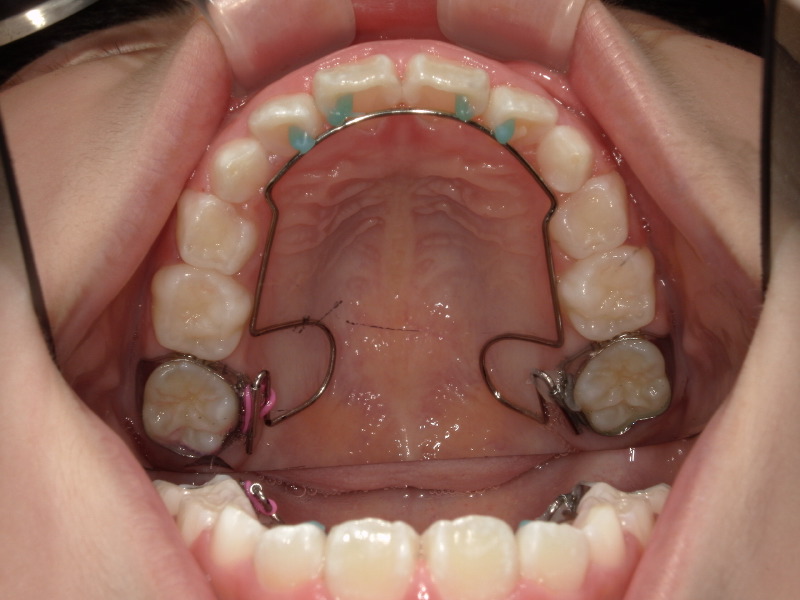

スタートから一年後の歯並びです。

初めは平坦気味だった2番目の歯もアーチに沿って綺麗になっています。

ですがまだ生え変わりがあることと、スペースに余裕はないため装置を装着しました。

歯と歯にしっかりと隙間ができて広がっています。

装置をつけると一時的に出っ歯っぽく見えていますがここからまた上顎は変わっていきます。

一度装置は外して様子を見ていたのですがまだスペースが欲しいため再度装置をつけました。

丸で囲っている歯が綺麗に入ることを目的とした装置にもなります。

装置が外れる頃には丸で囲った歯は綺麗に並んでいます。